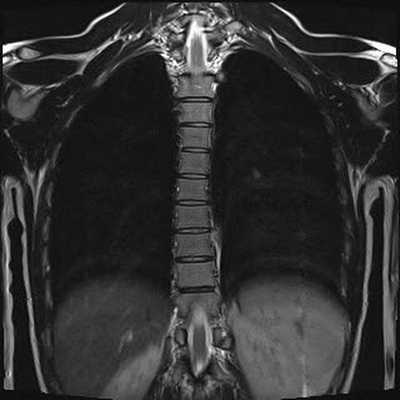

МРТ грудного отдела позвоночника в коронарной проекции

Гемангиомы на МРТ снимке грудного отдела позвоночника (сагиттальная проекция, Т2 взвешенное изображение)

Гемангиома на МРТ грудного отдела позвоночника, коронарная проекция